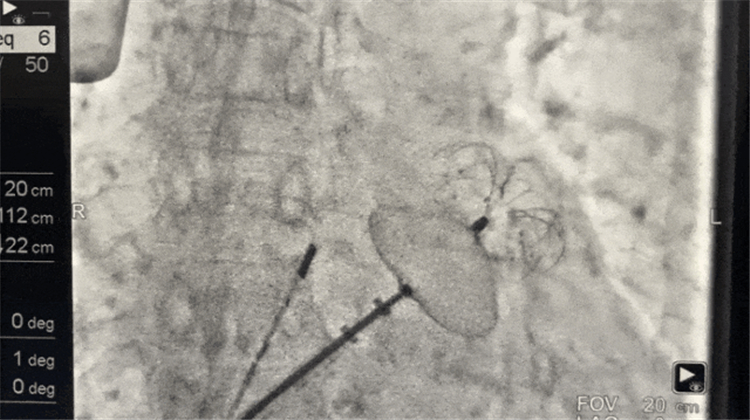

手术在局部麻醉下进行。团队在DSA及ICE引导下精准穿刺房间隔,清晰观察到左心耳内10mm×6mm的血栓。术中,团队评估左心耳形态与大小,选定合适的封堵器,顺利完成封堵操作。经多角度评估,封堵器位置形态良好,符合PASS原则,牵拉试验及多普勒扫描显示封堵完全,无残余分流,手术成功。

封堵器展开,左心耳血栓封堵手术成功。